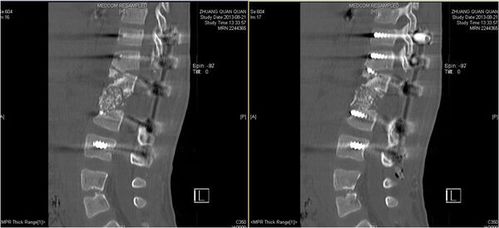

图2和图3是一个患有先天性脊柱侧弯的儿童,他的侧凸在手术后持续恶化.

> 正文 此例接受手术的患儿腰背部后凸畸形6年,诊断为先天性脊柱胸